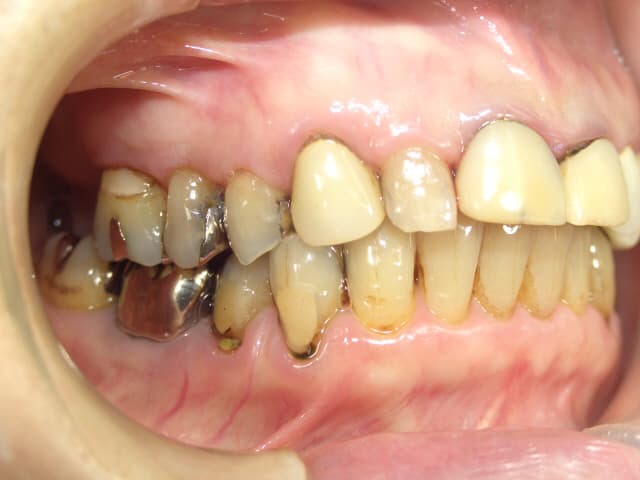

今回ご紹介する歯周治療のケースは、70代女性の方です。

歯周病は中等度で、歯ぐきの腫れや出血(BOP 80%以上)、口臭がありました。

また、被せ物も古くなり歯ぐきとの境目に段差が出来てしまい、2次虫歯も多く確認できました。